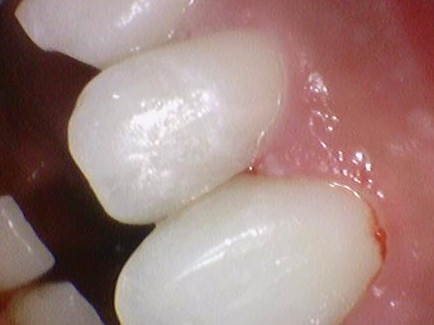

치료 전 사진입니다. 맞닿아있는 앞니 두치아에 충치가 생겨서 한치아는 이미 구멍이 생겨버렸고

한치아는 아직 구멍은 생기지않았지만 충치가 보입니다.